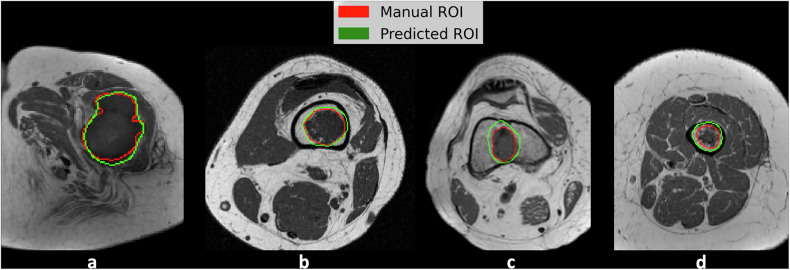

Materials and methods: This institutional review board-approved retrospective study included 164 patients with surgically treated and histology-proven cartilaginous tumors at two tertiary bone tumor centers. The first cohort consisted of 99 MRI scans from center 1 (79 ACT, 20 CS2). The second cohort consisted of 65 MRI scans from center 2 (45 ACT, 20 CS2). Supervised Edge-Attention Guidance segmentation Network (SEAGNET) architecture was employed for automated image segmentation on T1-weighted images, using manual segmentations drawn by musculoskeletal radiologists as the ground truth. In the first cohort, a total of 1,037 slices containing the tumor out of 99 patients were split into 70% training, 15% validation, and 15% internal test sets, respectively, and used for model tuning. The second cohort was used for independent external testing.

Results: In the first cohort, Dice Score (DS) and Intersection over Union (IoU) per patient were 0.782 ± 0.148 and 0.663 ± 0.175, and 0.748 ± 0.191 and 0.630 ± 0.210 in the validation and internal test sets, respectively. DS and IoU per slice were 0.742 ± 0.273 and 0.646 ± 0.266, and 0.752 ± 0.256 and 0.656 ± 0.261 in the validation and internal test sets, respectively. In the independent external test dataset, the model achieved DS of 0.828 ± 0.175 and IoU of 0.706 ± 0.180.

Conclusion: Deep learning proved excellent for automated segmentation of central cartilage tumors on MRI.